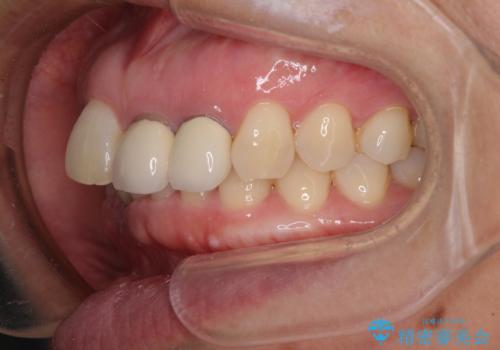

- 下顎前歯が抜けそうとのことで来院された患者様です。

初診の状態ではすぐにでも抜けそうな状態で、インプラントによる補綴治療を行うこととしました。

インプラント治療に際し、前歯の叢生に対する矯正治療を提案したところ、興味を持たれたので、インビザライン・ライトによる矯正治療を行うこととしました。

抜歯後にスペースができると恥ずかしいため、抜歯した歯を接着剤で固定した上で矯正治療を行い、その後インプラントやオールセラミッククラウンの装着を行うこととしました。